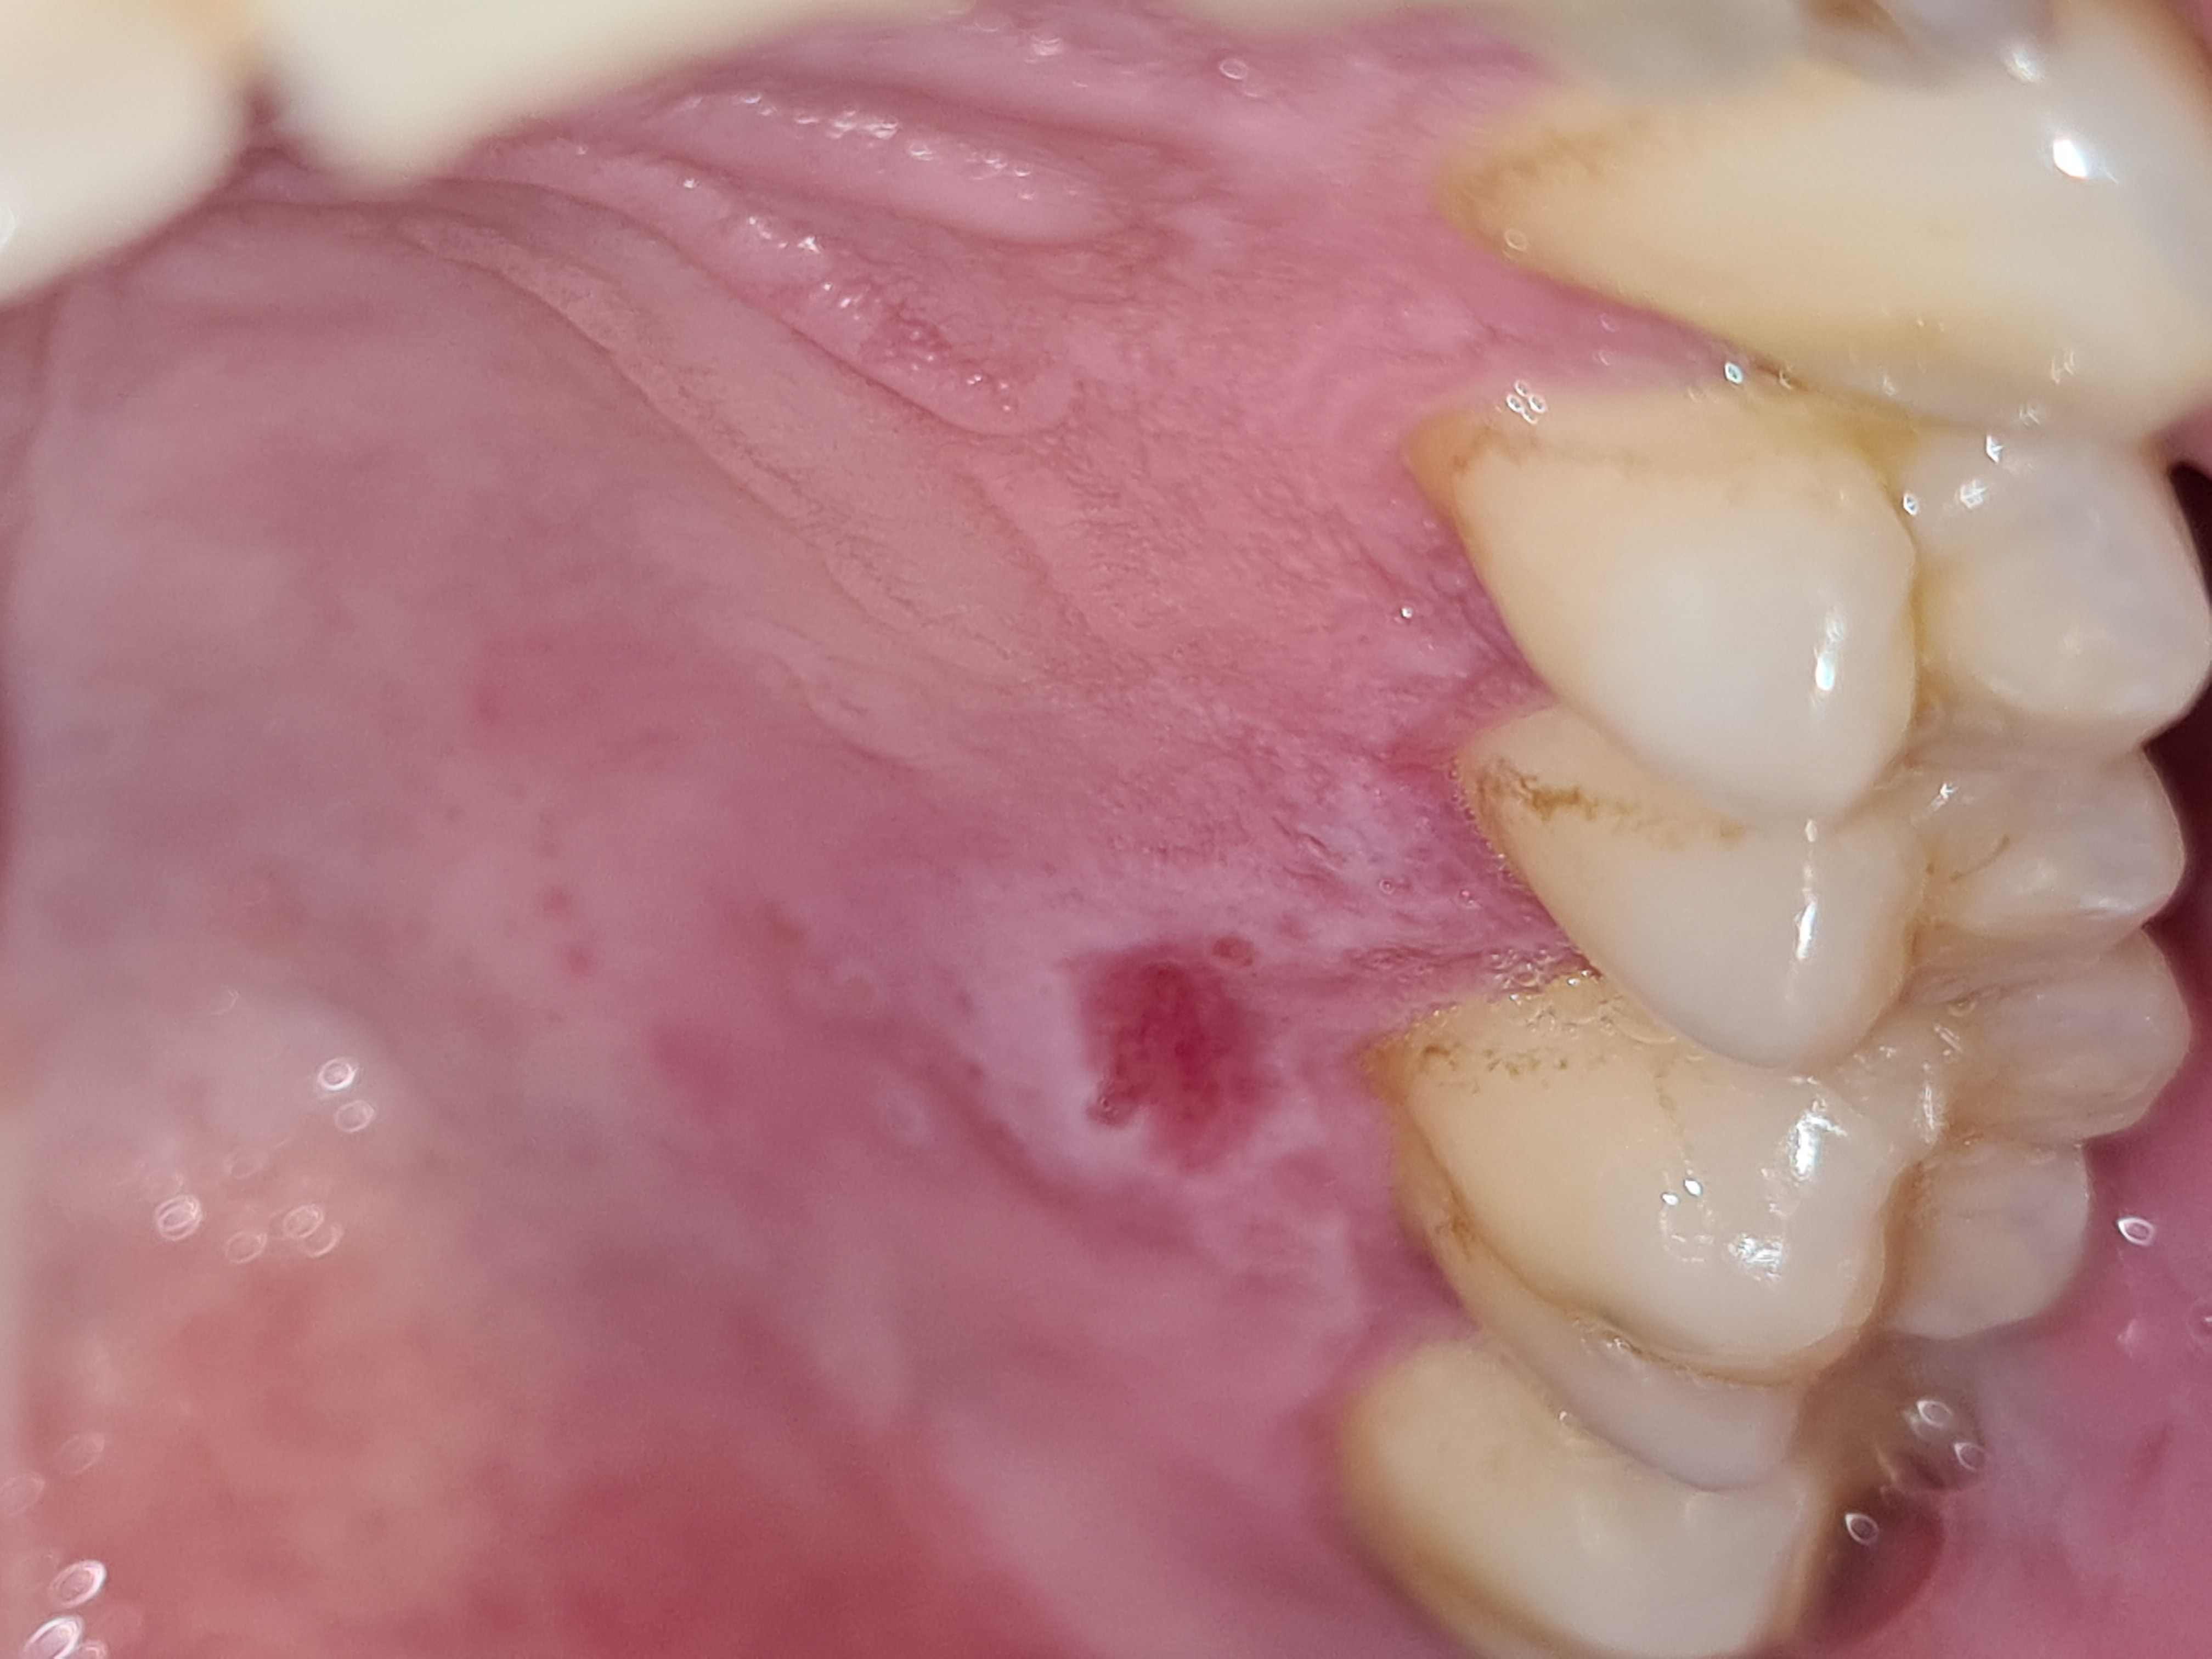

Buonasera Vi scrivo perché inizio a preoccuparmi un po per un'ulcera sul palato della bocca. È dolorosa e da circa una settimana mi da noie anche quando mangio. Ho preso appuntamento con il mio dentista di fiducia ma a causa covid devo aspettare altre due settimane. Questa cosa è comparsa dalla notte al giorno...e stranamente sembra che il fastidio arrivi fino al naso (non so se mi sono spiegato bene). Al contatto con la lingua è una zona liscia e solo lievemente rigonfiata. Sono un fumatore abituale di 38 anni. Allego un'immagine nella speranza che possiate quantomeno darmi qualche consiglio

Gentile Antonio, purtroppo attraverso una semplice foto non è possibile darle una risposta certa. Bisognerebbe eseguire una visita accurata, palpando anche la lesione per sentire la consistenza, vedere e sentire anche i bordi se sono induriti o morbidi come una mucosa normale e tante altre indagini non possibili da eseguire tramite internet. Però il fatto che, come lei dice, la lesione si è verificata rapidamente dalla notte al giorno questo propende più per una lesione benigna. Così ad occhio osservando la foto mi sembrerebbe come una lesione da scottatura o qualcosa che ha ferito al mucosa. Però le consiglierei di smettere assolutamente di fumare ed eliminare tutti i fattori irritanti per le mucose come ad esempio i superalcolici e se dopo 15 giorni la lesione è ancora in sede bisognerà ricorrere a un esame istologico per definire la natura della lesione stessa. Cordialmente